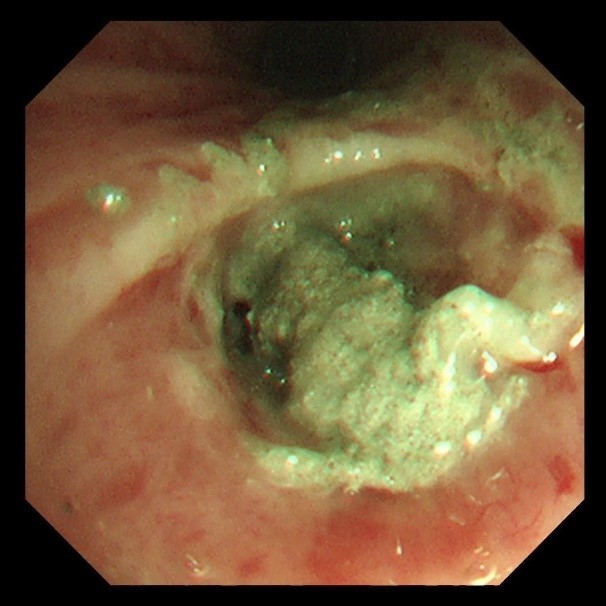

首次支气管镜清除手术:解决大块异物阻塞。因患者颈部有损伤,未行硬镜置入,在麻醉手术科的密切配合下,为患者经口插入8.5号气管插管,接呼吸机辅助通气,建立稳定的呼吸通道。随后,气管镜顺利进镜,发现气管及左主支气管内充满泥沙样分泌物、黄脓痰及块状异物。随后,实行精准操作:用吸引器清除泥沙样物质及黄脓痰;使用活检钳分次取出左下叶大块石状异物,并配合取石网篮清理;刷检带出细小碎石,并进行多部位生理盐水灌洗,最大限度清除可见异物。

(超细支气管镜见左下叶背段远端支气管泥沙样物质)